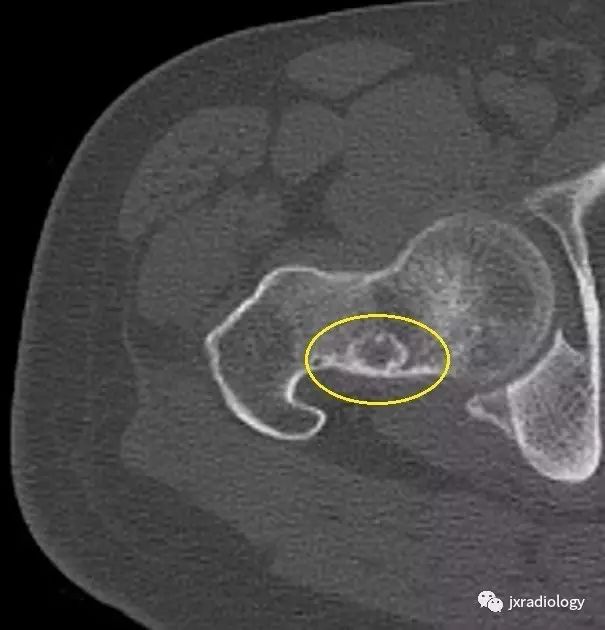

影像表现:X 线平片上表现为伴有清晰薄层硬化缘的环形(囊状)透亮区,CT 上表现为圆形 或类圆形的皮质下局灶性骨质缺损,周围见薄层硬化带环绕,边缘锐利,部分较大病灶在病灶层面或上下相邻、层面上前方显示皮质与病灶相通的局部裂隙样缺损病灶,最大径线通常小于 10 mm;MRI 示病灶在 T1WI 上呈低信号,在 T2WI 上呈均匀或不均匀高信号。

鉴别诊断:X 线平片对股骨颈疝窝具有初步诊断价值;依据典型的CT和/或MRI影像学表现,对股骨颈疝窝多可以作出准确的诊断。需要与骨内的腱鞘囊肿相鉴别:是一相邻关节的囊性病变,内衬滑膜细胞并含有粘液样物质,有时液体内蛋白质较高在T1W 上信号趋向升高。